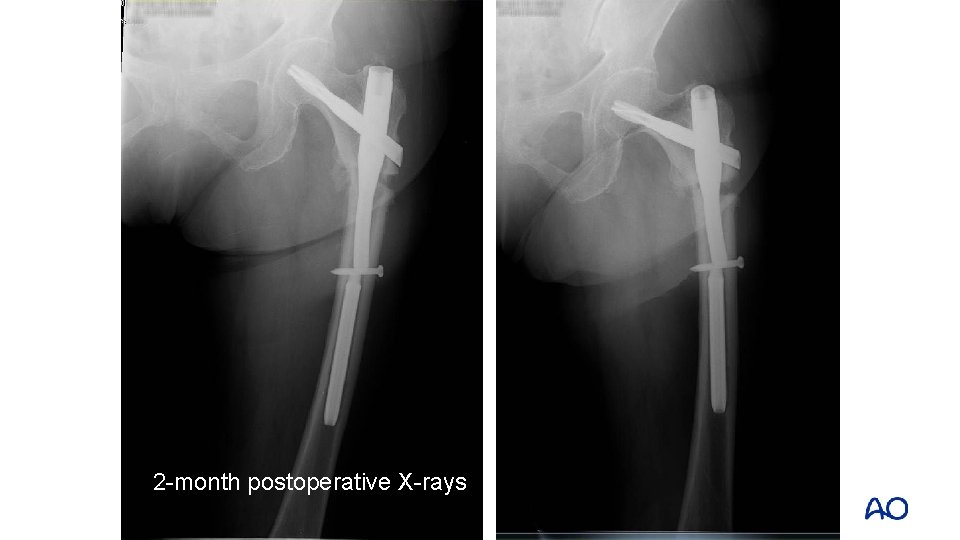

2 -month postoperative X-rays

• Back to Hong Kong • Left thigh pain, significant limping 6 -month postoperative x-rays

• Back to Hong Kong • Left thigh pain, significant limping Normal erythrocyte sedimentation rate (ESR), C-reactive protein (CRP), white cell count, no clinical evidence of infection

What is the cause? • Poor biology? • Poor stability? • Both?